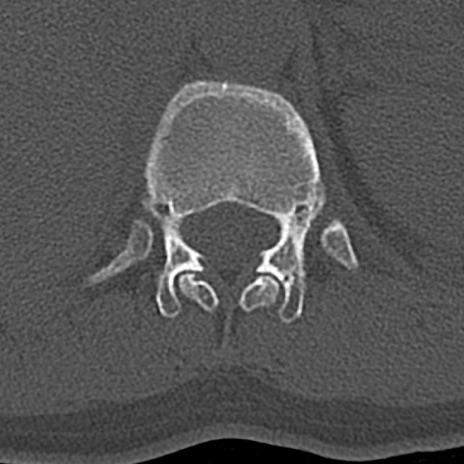

腰椎CT

横断像と矢状断像